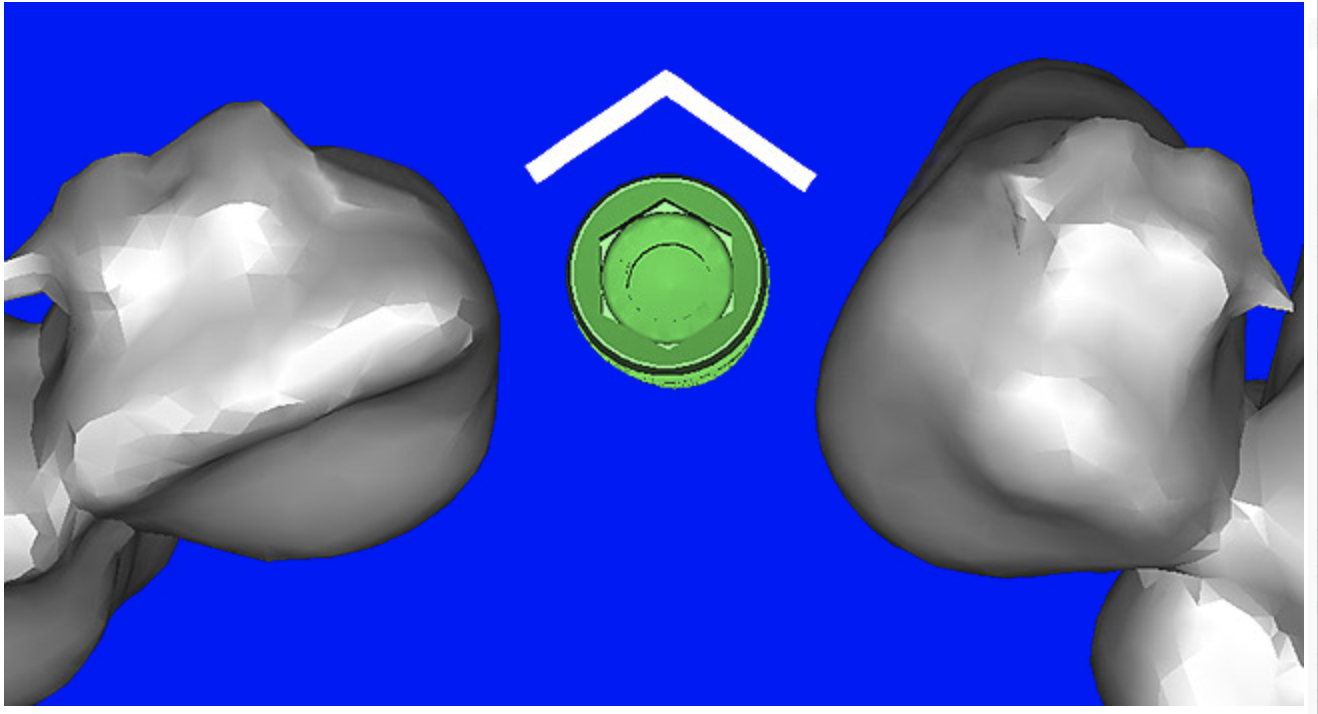

Using the interactive treatment-planning software application, the scan data was assimilated and both potential lateral incisor implant receptor sites were evaluated. It is a combination of the data and the methodology used to interpret the data that is the basis for defining a new paradigm in diagnosis and treatment planning. Proper evaluation of these images and correct use of the interactive treatment-planning software tools is essential in creating a decision tree of treatment options. First, the data from the scan was reformatted into panoramic, axial, and cross-sectional images. The undistorted cross-sectional images revealed the residual alveolar bone in the area of the right lateral incisor. Then, a simulated schematic implant was placed within the bone with an abutment extension to help visualize the connection to the restorative position of the tooth (Figure 4A). The Triangle of Bone® (TOB), a concept developed by the author to analyze bone quality, quantity, and disposition at prospective dental implant sites using CBCT scans, aided in determining available bone volume by defining a “zone” for proper implant placement18,19 (Figure 4B).

After reviewing the CT data and the decision tree, the bone within the “zone” of the TOB was evaluated and found to be satisfactory for implant placement. Because the goal of implant dentistry is not the implant but the tooth that is placed, true restorative-driven implant dentistry must begin with the assumption that the implant position should remain consistent with the tooth it is replacing, and the final implant-supported restoration.12,22-26 The TOB aids the clinician in understanding the link between the implant position and the desired restorative goal. The base of the geometric shaped “zone” is visualized by starting at the widest area of alveolar bone facially and superiorly. The apex of the triangle is positioned to bisect the alveolar crest (Figure 4B). The TOB, the overlay in the cross-sectional image, reveals whether adequate bone is available for implant placement. It also helps to identify concave facial bone defects, and accurately determine the width of bone at the crest. The author recommends using an interactive software application that provides the necessary measurement tools to accurately assess the bone anatomy.

Figure 4b  CT scan data was input into the treatment-planning software, which allowed (A) placement of a simulated implant and (B) the determination of the “zone” for proper placement.

Figure 4b